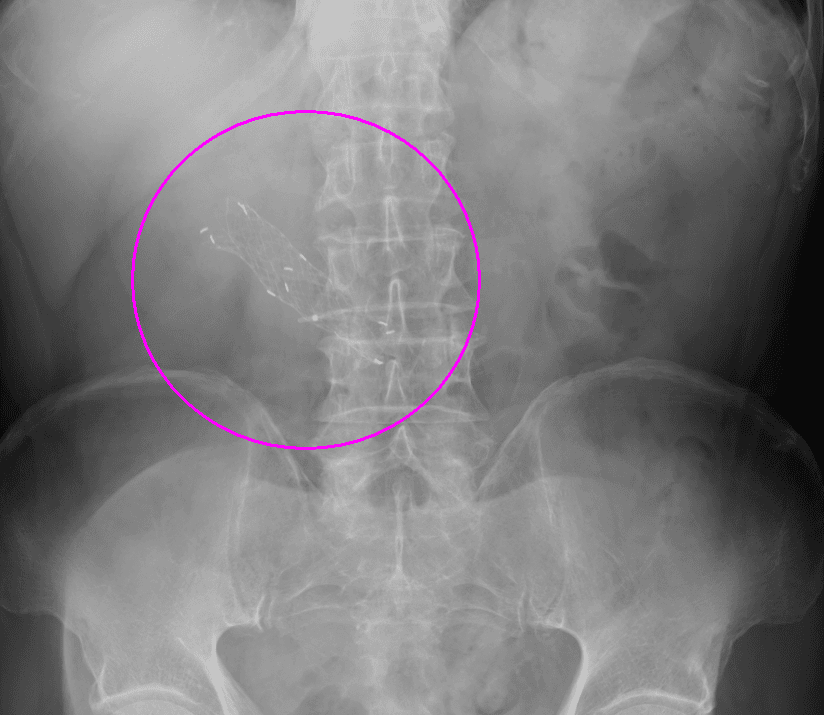

閉塞性大腸がんに対する大腸ステント治療

大腸がんが進行し腸が詰まってしまう閉塞性大腸がん(大腸がん腸閉塞)に対する治療です。従来は人工肛門を造設して対処していましたが、人工肛門はケアの負担やにおいに対する不安などからQOL(生活の質)低下が避けられません。そのため当院ではステントと言われるメッシュ構造の金属製の網を用いて詰まりを解消し、人工肛門を回避する治療を行っています。大腸ステント治療は緩和治療を目的に行う場合と根治手術前に全身状態の回復を目的として行う場合があります。

ステント留置後(内視鏡画像)

ステント留置後(レントゲン画像)